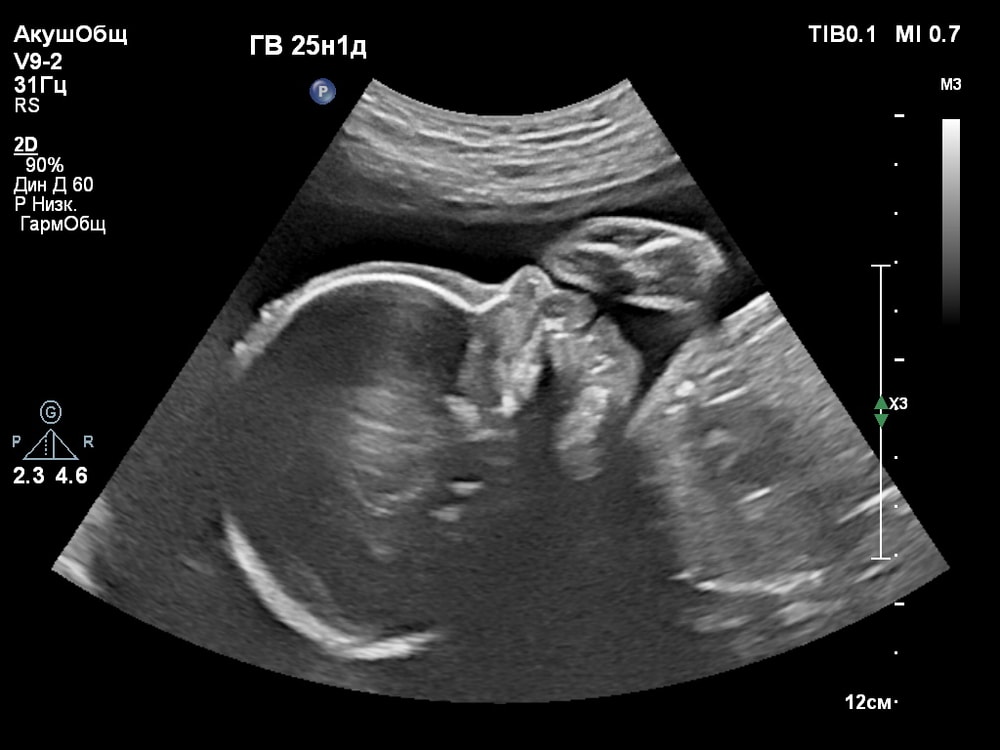

3D/4D УЗИ в 25 недель

УЗИ, КТГ, доплерПервая фотосессия малыша ещё в животике!😍 СНИМКИ С УЗИ👇

На приём приехала заранее с мужем, меня оформили, пришлось немного подождать, пока другой клиент выйдет. По времени приём длится 30 мин. Оплата производится после УЗИ. В цену входит 4D исследование, полноценное 2D исследование, заключение УЗИ, 3 распечатанные 3D снимка на спец бумаге в чёрно-белом (все остальные фото в цвете присылают в этот же день на указанную почту). Как оказалось УЗИ аппарат не записывает 4D видео, а только показывает, поэтому видео записывал муж на телефон.

Когда переключили на 4D режим было сначала непонятно, что изображено на экране. Но врач всё показывала и обьясняла что на нём: где носик, губки, подбородок, что у личика ручки, малыш что-то жуёт, губками шевелит. Тогда картина начала вырисовываться и всё стало понятно, и в движении тоже)).

За 30 мин удалось увидеть многое (ребёночек не спал)! Он у меня в принципе парень активный, особенно лёжа на спине): на УЗИ, ещё в самом начале, малыш показал указательный палец и почесал им нос 😂, потом пытался большой палец засунуть в рот и пососать. Забавно было, когда он начал зевать и прикрывать ротик ладонью (воспитанный растёт). Ну и конечно, на радость родителям малыш улыбался🥰. Александра Евгеньевна смогла поймать все эти моменты и запечатлеть на снимке). Когда ребёночек закрывался, отворачивался - врач проводила общее 2D исследование, потом возвращалась к 4D.

Иногда получить хорошую картинку сложно. Качество изображения сильно зависит от положения плода, количества околоплодных вод, расположения плаценты, толщины брюшной стенки. Мне в этом плане повезло, плацента была расположена по задней стенке матки, брюшная стенка у меня тоненькая, околоплодные воды в норме, малыш был в движении и можно было разглядеть его профиль.